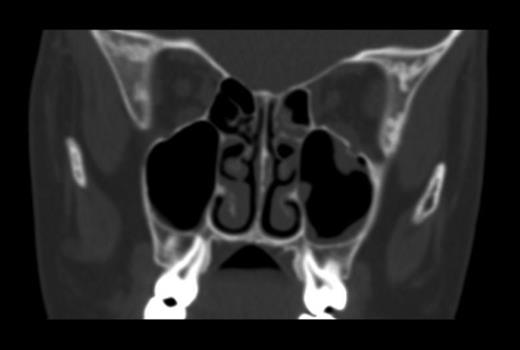

He had minimal periorbital bruising, and his visual acuity was 6/6; however, his ability to move his eye was reduced over the next 24h, and his diplopia worsened. His nausea and vomiting continued, and he had a head CT scan performed. This showed no brain injury; however, the scan discovered a left orbital floor fracture with entrapment of the inferior rectus muscle (Fig. 1).

Preoperative CT scan showing a fracture of the left orbital floor with entrapment of the inferior rectus muscle.